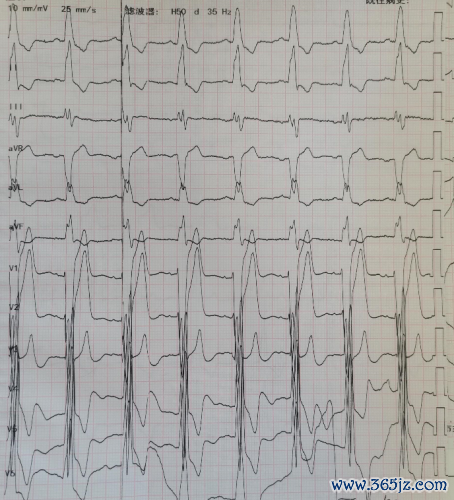

心电图:窦性心律,澈底性左束支进犯(图1)。

图1 心电图